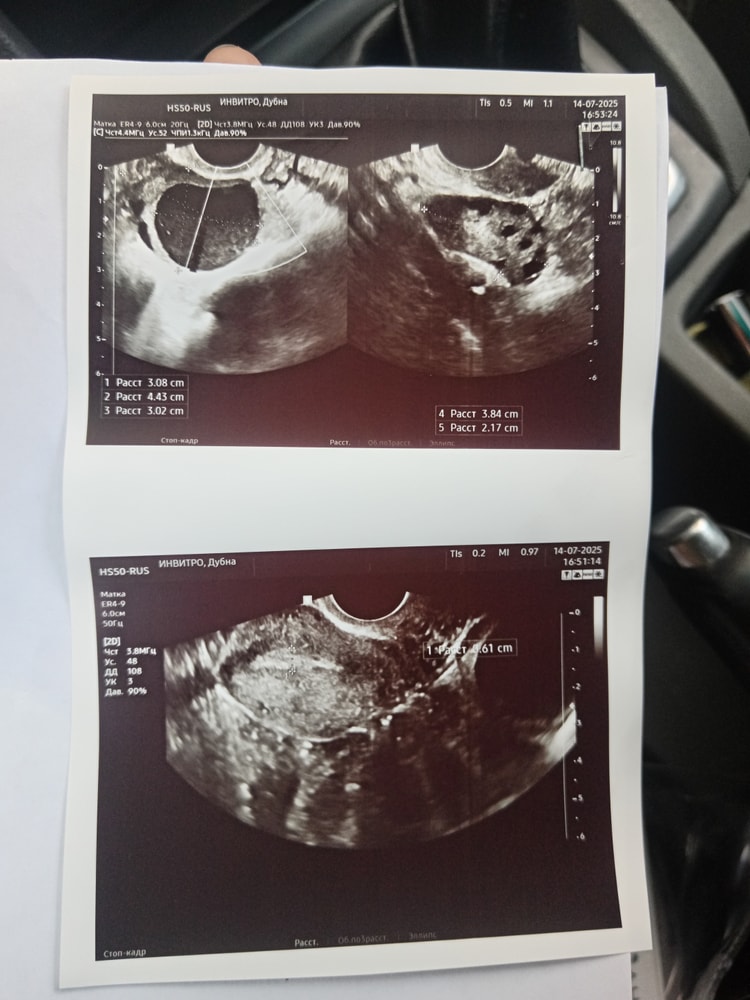

Здравствуйте. Может, кто подкованнее здесь. 17 день цикла. В одном яичнике узист написала киста, не знает какая, думает фолликулярная. А во втором что такое тёмное слева? Может быть желтое тело такое или напрасные надежды, что внезапно вырос за неделю и совулировал какой фолликул? Была неделю назад на узи, там где киста, был фолликул 13мм. А в другом толлко 9-10фолликулов по 10мм. Вдруг какой из них?

Жидкости за маткой сейчас не увидела.

Мне кажется это ЖТ. С 13 до 20 вполне мог дорасти за неделю и в 20мм лопнуть

Простите, не так поняла вопрос. В теории и с 9 мог дорасти. Но это уже и не важно. Если киста, то это не отменяет возможную беременность: овуляция была так что все возможно. Я думаю так, но я не врач